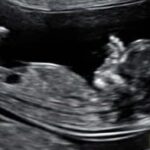

Αυχενική Διαφάνεια / Papp-A